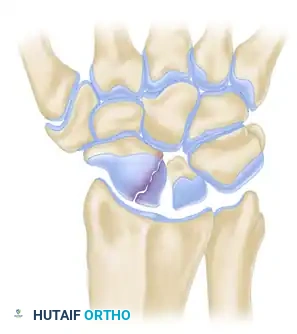

Surgical Anatomy and Fracture Classification

Understanding the three-dimensional orientation of the scaphoid is paramount for successful percutaneous fixation. The scaphoid lies at an oblique angle—approximately 45 degrees to both the sagittal and coronal planes of the wrist.

Fractures are generally classified by their anatomic location: distal pole, waist (middle third), and proximal pole. Waist fractures are the most common, accounting for 70-80% of all scaphoid fractures. Proximal pole fractures have the highest rate of nonunion and osteonecrosis due to the retrograde blood supply.

Scaphoid Fracture Displacement

Clinical Pearl: The central axis of the scaphoid is the biomechanically optimal position for screw placement. A screw placed down the central third of the scaphoid provides maximum stiffness, highest load to failure, and optimal compression across the fracture site.